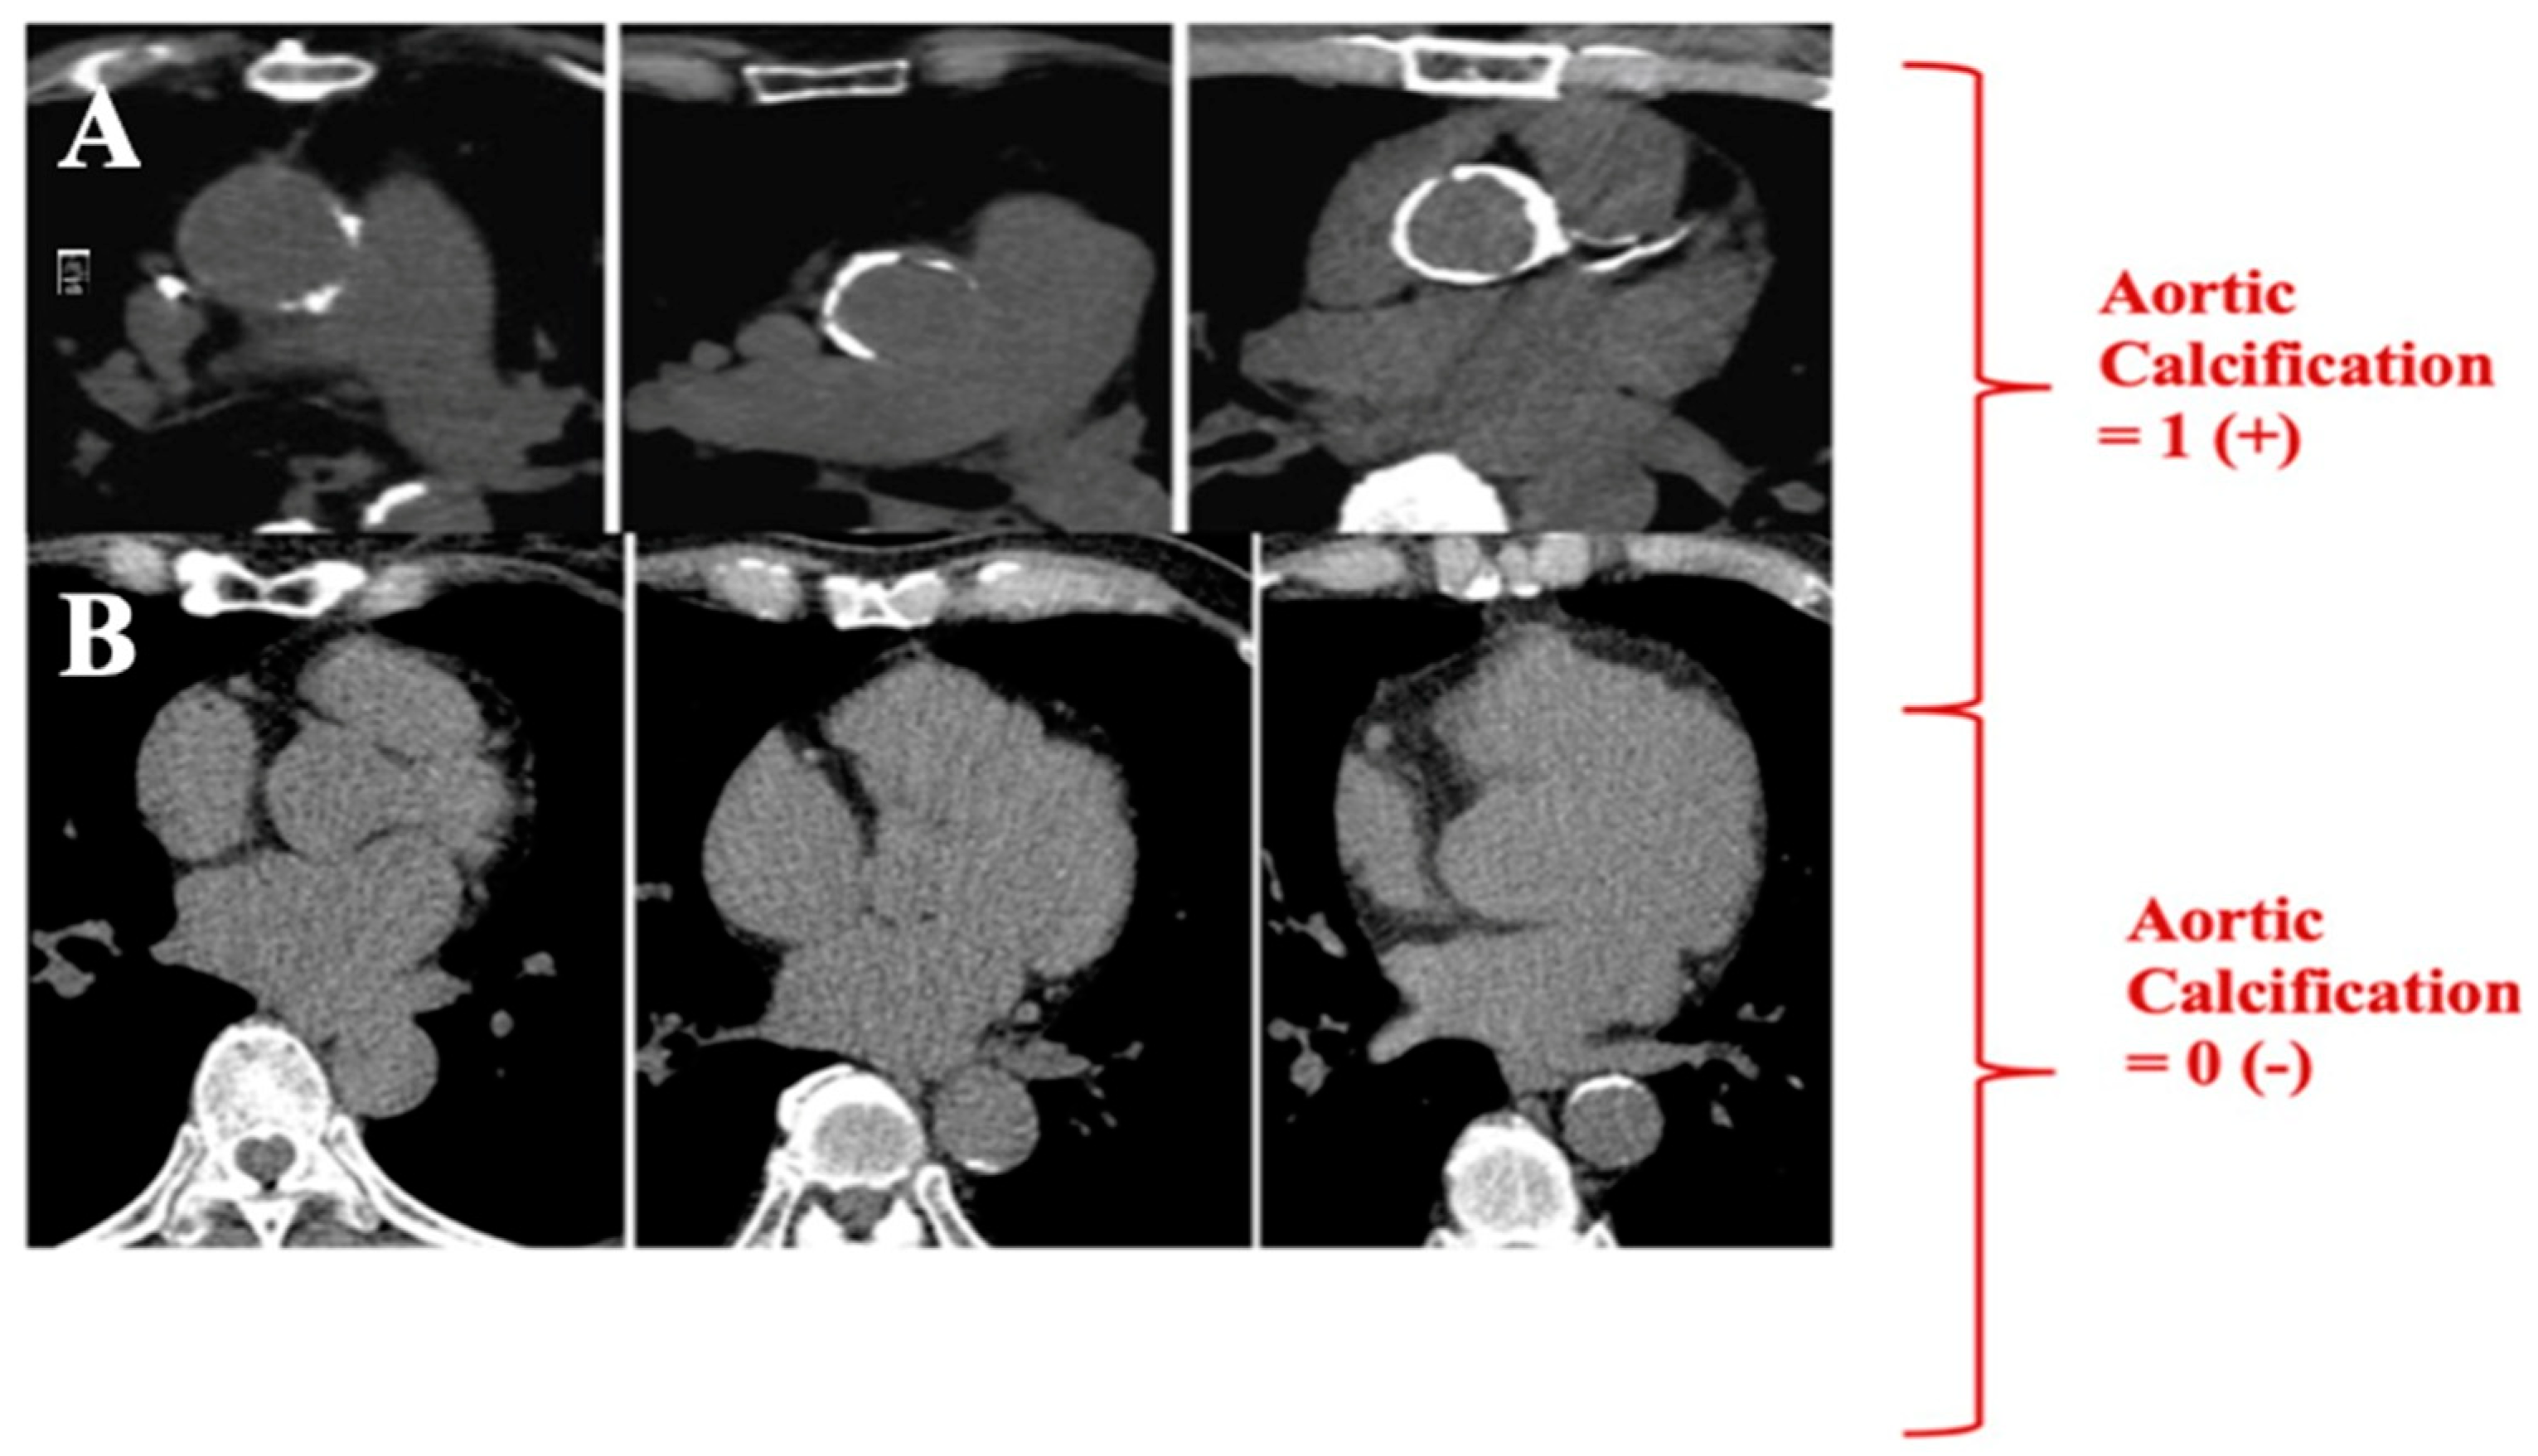

| HEARRT-C Score | ||

|---|---|---|

| H | Haemoglobin < 12 g/dL | 1 point |

| E | Elderly (age) > 67 years | 1 point |

| A | ASA (not receiving) | 2 point |

| R | Rate (heart rate > 100 bpm) | 1 point |

| R | Respiration (saturation < 90%) | 1 point |

| T | hsT ≥ 9.5 ng/L (on admission) | 2 point |

| C | CACS + Aort calcification + | 1 point |

| Total points: | >5 |